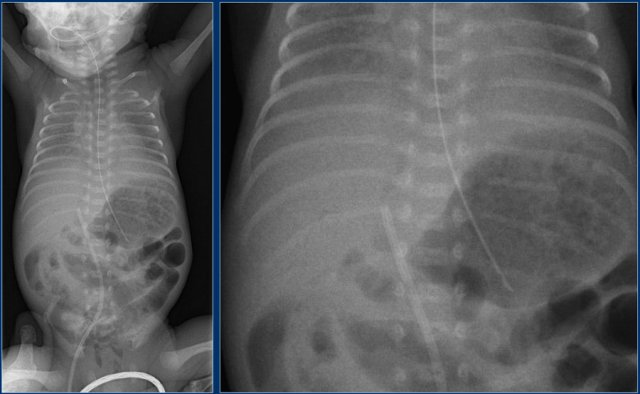

Umbilical artery line (2)

First study the images.

Then continue reading.

The findings are:

1. Umbilical artery line in a good high position.

2. Malposition of umbilical vein line in right portal vein.

3. Skin folds over right basal thorax, which should not be mistaken for a pneumothorax. They typically do not follow anatomical borders.